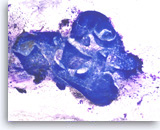

Chronic pancreatitis, Pancreas FNA, Cell Block

Benign pancreatic acinar cells are intermixed with fragments of fibrous tissue and lymphoplasmacytic infiltrates. The acinar cells are small and arranged in an acinar pattern. Note relatively preserved lobular appearance of pancreatic acini.

20X